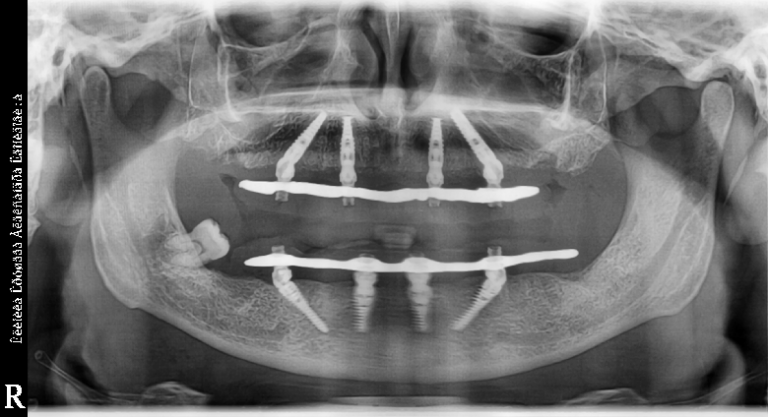

При недостаточном объеме костной ткани, хронических заболеваниях, ограниченном пространстве десны и т.д. понадобится имплантат с особыми техническими характеристиками. Например, мы используем такие при несъемном протезировании TiS.

Несъемное протезирование TiS на 2 челюстях

У бюджетных моделей, как правило, больше противопоказаний или ограничений к установке. К примеру, если нужны зубные протезы на 4 имплантах, в большинстве случаев нельзя будет воспользоваться продукцией дешевых брендов.